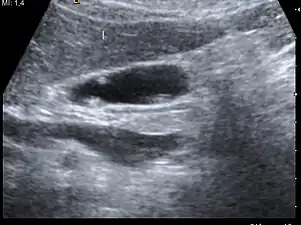

Ultrasound image of gallbladder polyps measuring 3–7 mm.